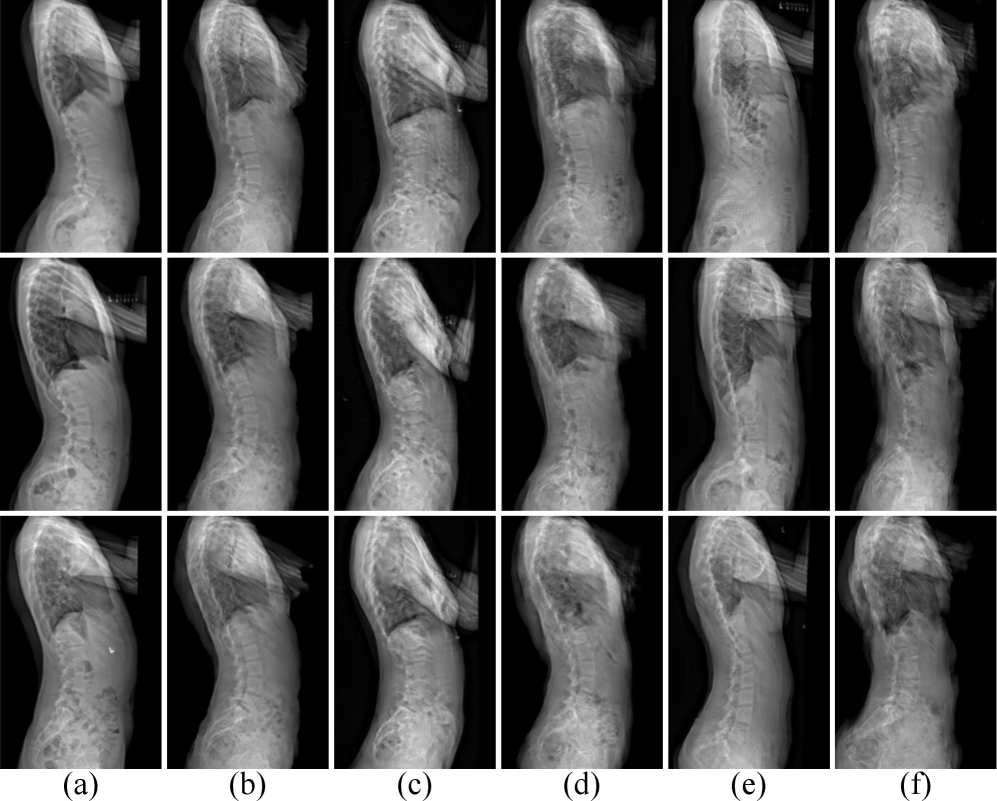

Refer to caption

Figure 5: Visual comparison of lateral spinal radiograph synthesis. The six columns are: (a) GT radiograph, (b) LatXGen, (c) LatXGen replace the LRS with Pix2PixGAN, (d) LatXGen replace the LRS with Pix2PixHDGAN, (e) Pix2PixGAN, and (f) Pix2PixHDGAN.

5.2 Lateral Spinal Radiograph Synthesis

Fig. 5 presents a visual comparison of lateral spinal radiographs synthesized by different generator architectures. To evaluate the effectiveness of the proposed LRS module, we retained the overall LatXGen framework and varied only the generator within the LRS stage, testing three configurations: our proposed LRS module, Pix2PixGAN, and Pix2PixHDGAN. Their respective results are shown in Fig. 5 columns (b), (c), and (d). As shown, the proposed generator in LRS stage produces more anatomically realistic results in the spinal regions, with clearer vertebral boundaries. In contrast, Fig. 5 columns (e) and (f) display results from standalone Pix2PixGAN and Pix2PixHDGAN models applied directly to lateral spinal radiograph synthesis. These outputs exhibit noticeable structural distortions, including exaggerated vertebral wedging and, in the case of Pix2PixHDGAN, failure to capture coherent spinal anatomy (the generated spinal regions are blurred). Comparing columns (c) vs. (e) and (d) vs. (f) highlights the advantage and benefits of LatXGen’s progressive architecture, i.e., first estimating the spine curve and then synthesizing the radiograph based on the curve. The dual-stage generation strategy enables more accurate modeling of sagittal spinal morphology. Quantitative metrics evaluating the image generation quality across the different models and configurations are presented in Table 2. The LRS module processes each image in about 0.05 seconds on average and consumes about 0.8 GB of GPU memory. Although these measures are widely used benchmarks, they may be affected by non-spinal regions. To highlight clinical relevance, we also report sagittal parameters (TKA, LLA, SSA) from the synthesized radiographs as complementary validation of the model’s effectiveness.